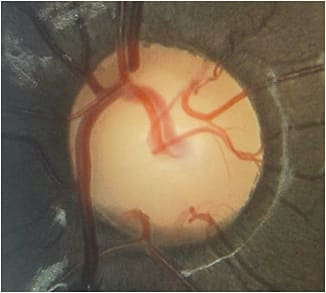

Evaluate the optic disc and nerve fiber layer (NFL) for defects. A normal NFL has a striate appearance with underlying vessels obscured, as if a transparent tape is placed over the vessels. NFL defects extend to the disc and can be in a slit, wedge or diffuse pattern. Also, be aware of optic nerve head notching, which appears as focal loss of tissue and vertical elongation and narrowing of the neuroretinal rim, commonly superiorly and inferiorly. In addition, disc hemorrhages should be a red flag for glaucoma. Major studies, including the Early Manifest Glaucoma Trial, indicate that disc hemorrhages are strongly associated with glaucoma progression. Finally, keep an eye out for vascular changes, such as a bayonet sign and vessel baring. The former shows retinal vessels deviating from their normal course. A “z” appearance is common, as vessels emerge at a sharp angle over the edge of the cup. The latter shows that vessels are no longer supported by rim tissue and have an appearance of being suspended over free space.